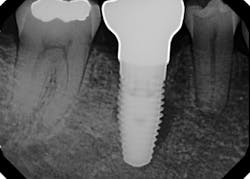

I began centering my consultation appointments on options that subsequently allowed patients to actually sell themselves on the implant treatment modality. I would present the tooth-replacement options of endo/core/crown, extraction/bridge, and extraction/implant ... and then I would explain the pros and cons of each. What I found is that patients overwhelmingly chose the root-replacement option—dental implants—over the old-school (drill-o-dontics) to reconstruct their missing tooth. Patients actually wanted an implant once they were armed with all the complete information they needed to make their decision. Having models on hand that show the difference between each option is highly effective, especially for those patients who are visual learners.

When your treatment plan includes only the next most conservative procedure—instead of all treatment options—inevitably you will do lots of work “saving” badly damaged roots and roots with guarded or poor long-term prognosis. Some patients may applaud or highly value these efforts on your part, but I have met many more who are glad to skip the possibility of re-treatment, root fracture, core failure, etc. You'll find that many patients will choose implants as an expedient and efficacious alternative to restoring the root with diminished or guarded prognosis, rather than spend their money over and over again on an undesirable tooth.

This is the paradigm shift in thinking that initiated big changes in my practice. In 2010, my little office restored 38 implant fixtures. By 2017, we were restoring closer to 200. What a difference! When patients began to realize they had treatment possibilities that may have a better long-term prognosis than the traditional replacement options, implants became a definite green light for them.